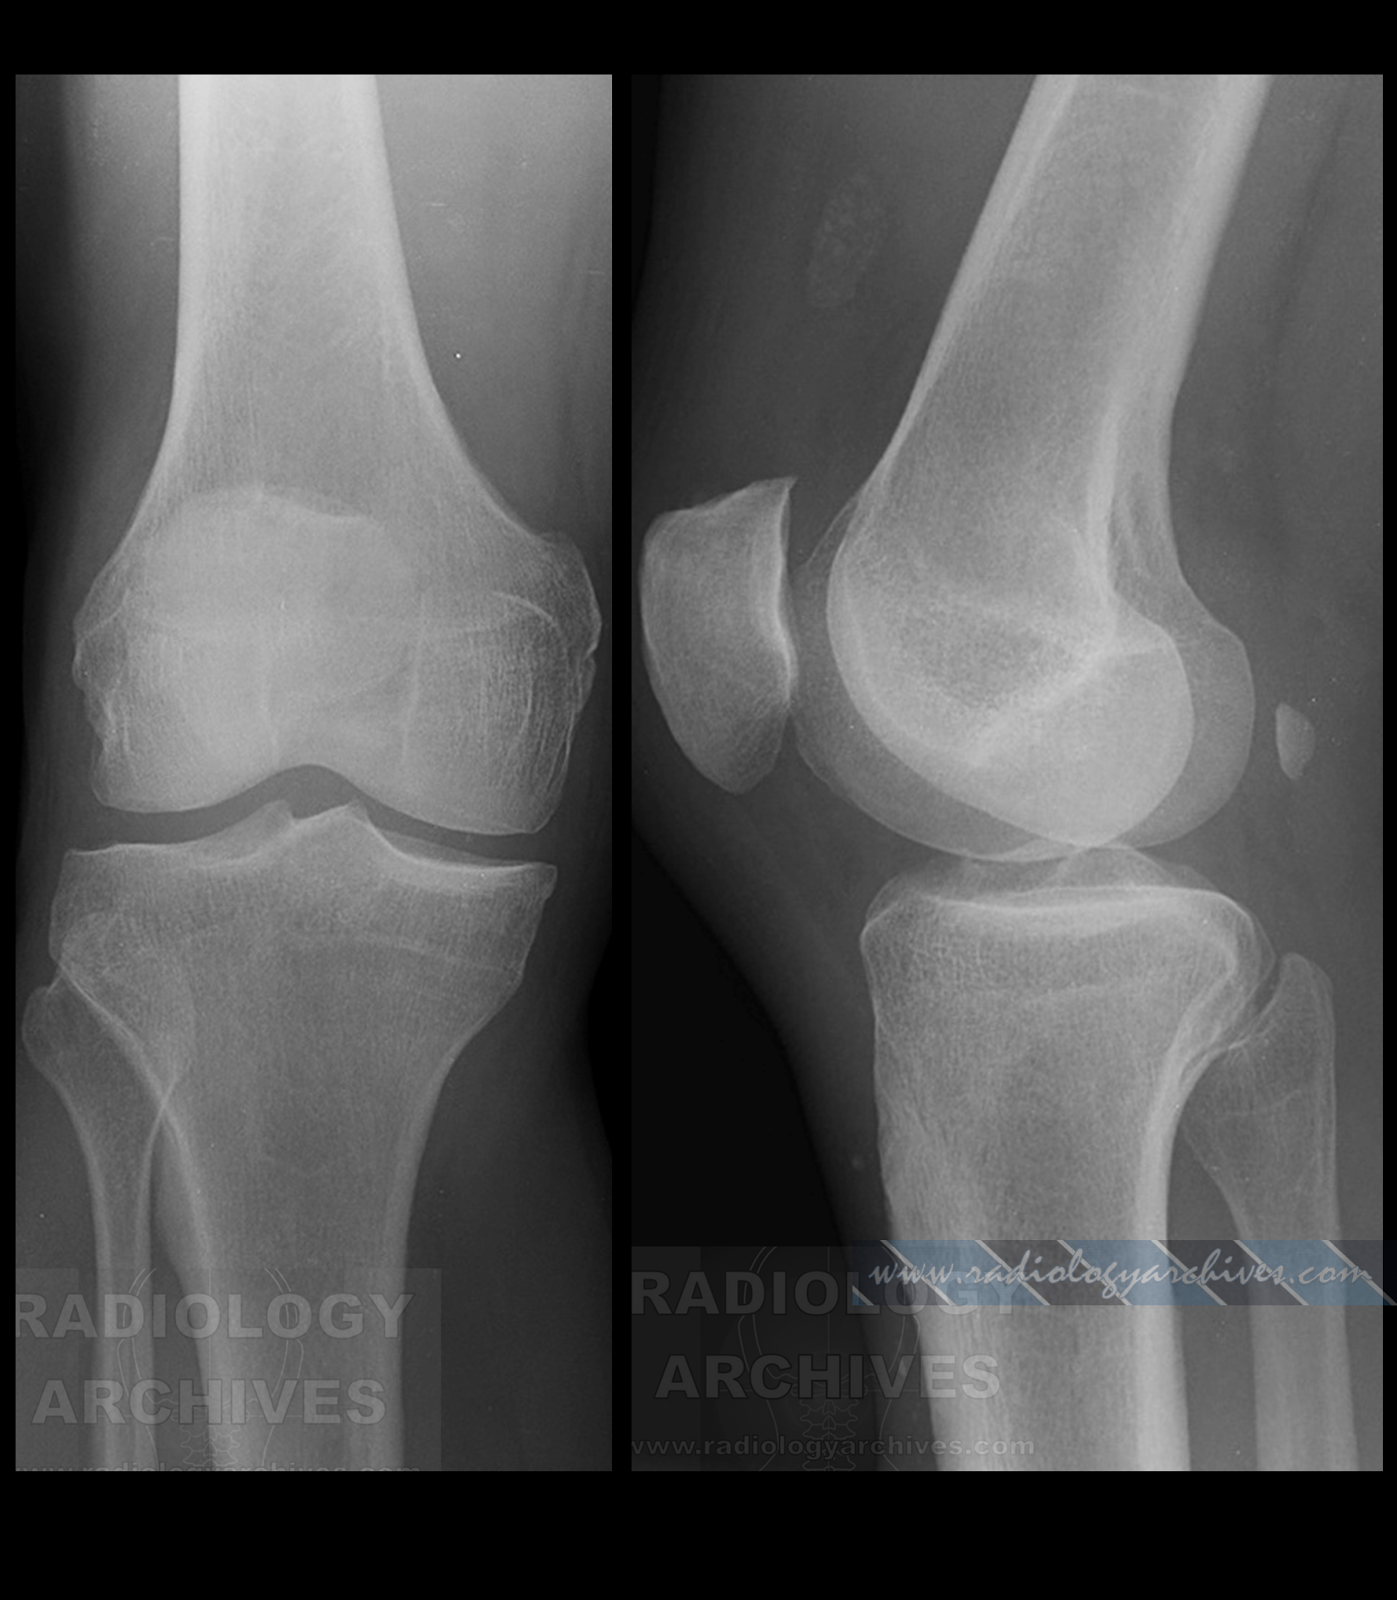

Строение и роль сесамовидной косточки в коленном суставе